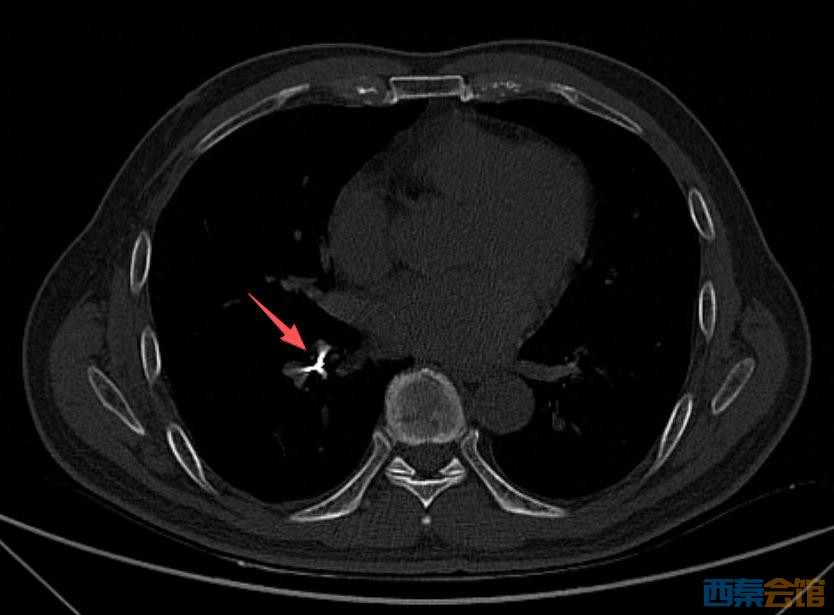

随后,诊所牙医陪同男子到北海市人民医院就诊,经 CT 检查,在患者右下肺支气管内发现有异物存留,便紧急收入呼吸与危重症医学科病房。

病房接诊后,医院立即启动急诊救治流程。医疗团队为患者取出异物,

经确认,取出的异物正是用于根管治疗的机扩针,长约 2 厘米,针的一头圆滑、一头细长而尖锐。

“幸好是圆滑的一头朝下滑进气管,一路滑到支气管没有造成意外损伤。”事后,医生表示。